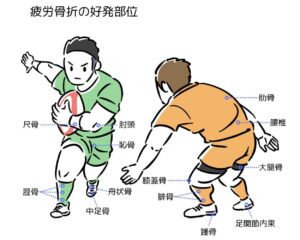

上肢から下肢、体幹とあらゆる部分の骨に起こり、年齢を問わず発生します。発生部位は競技種目や各スポーツ動作と関連が強く、脛骨や中足骨など下肢での発生が多いですが、MRIやCTの普及により腰椎疲労骨折(腰椎分離症)の頻度が最も高いとの報告もあります。